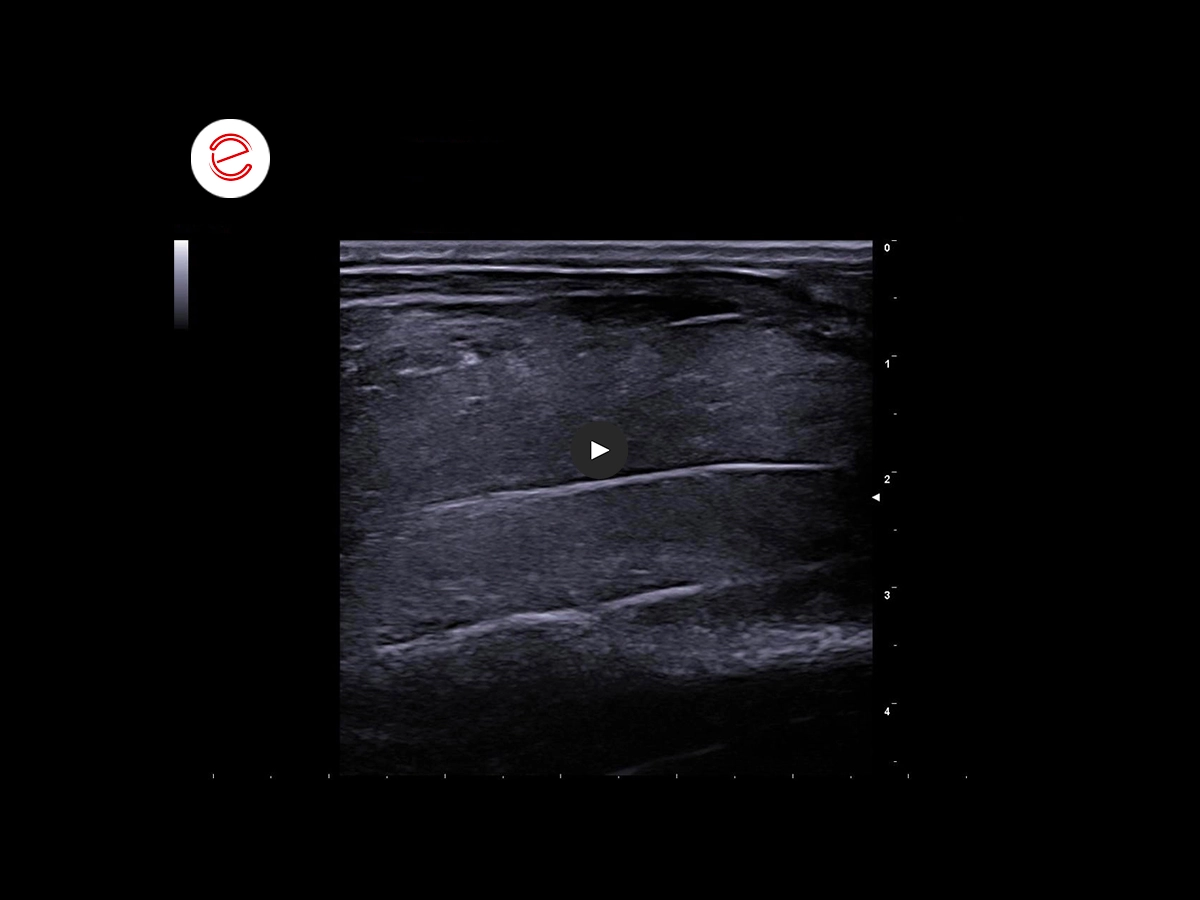

The ultrasound image shows the supraspinatus muscle is healthy.